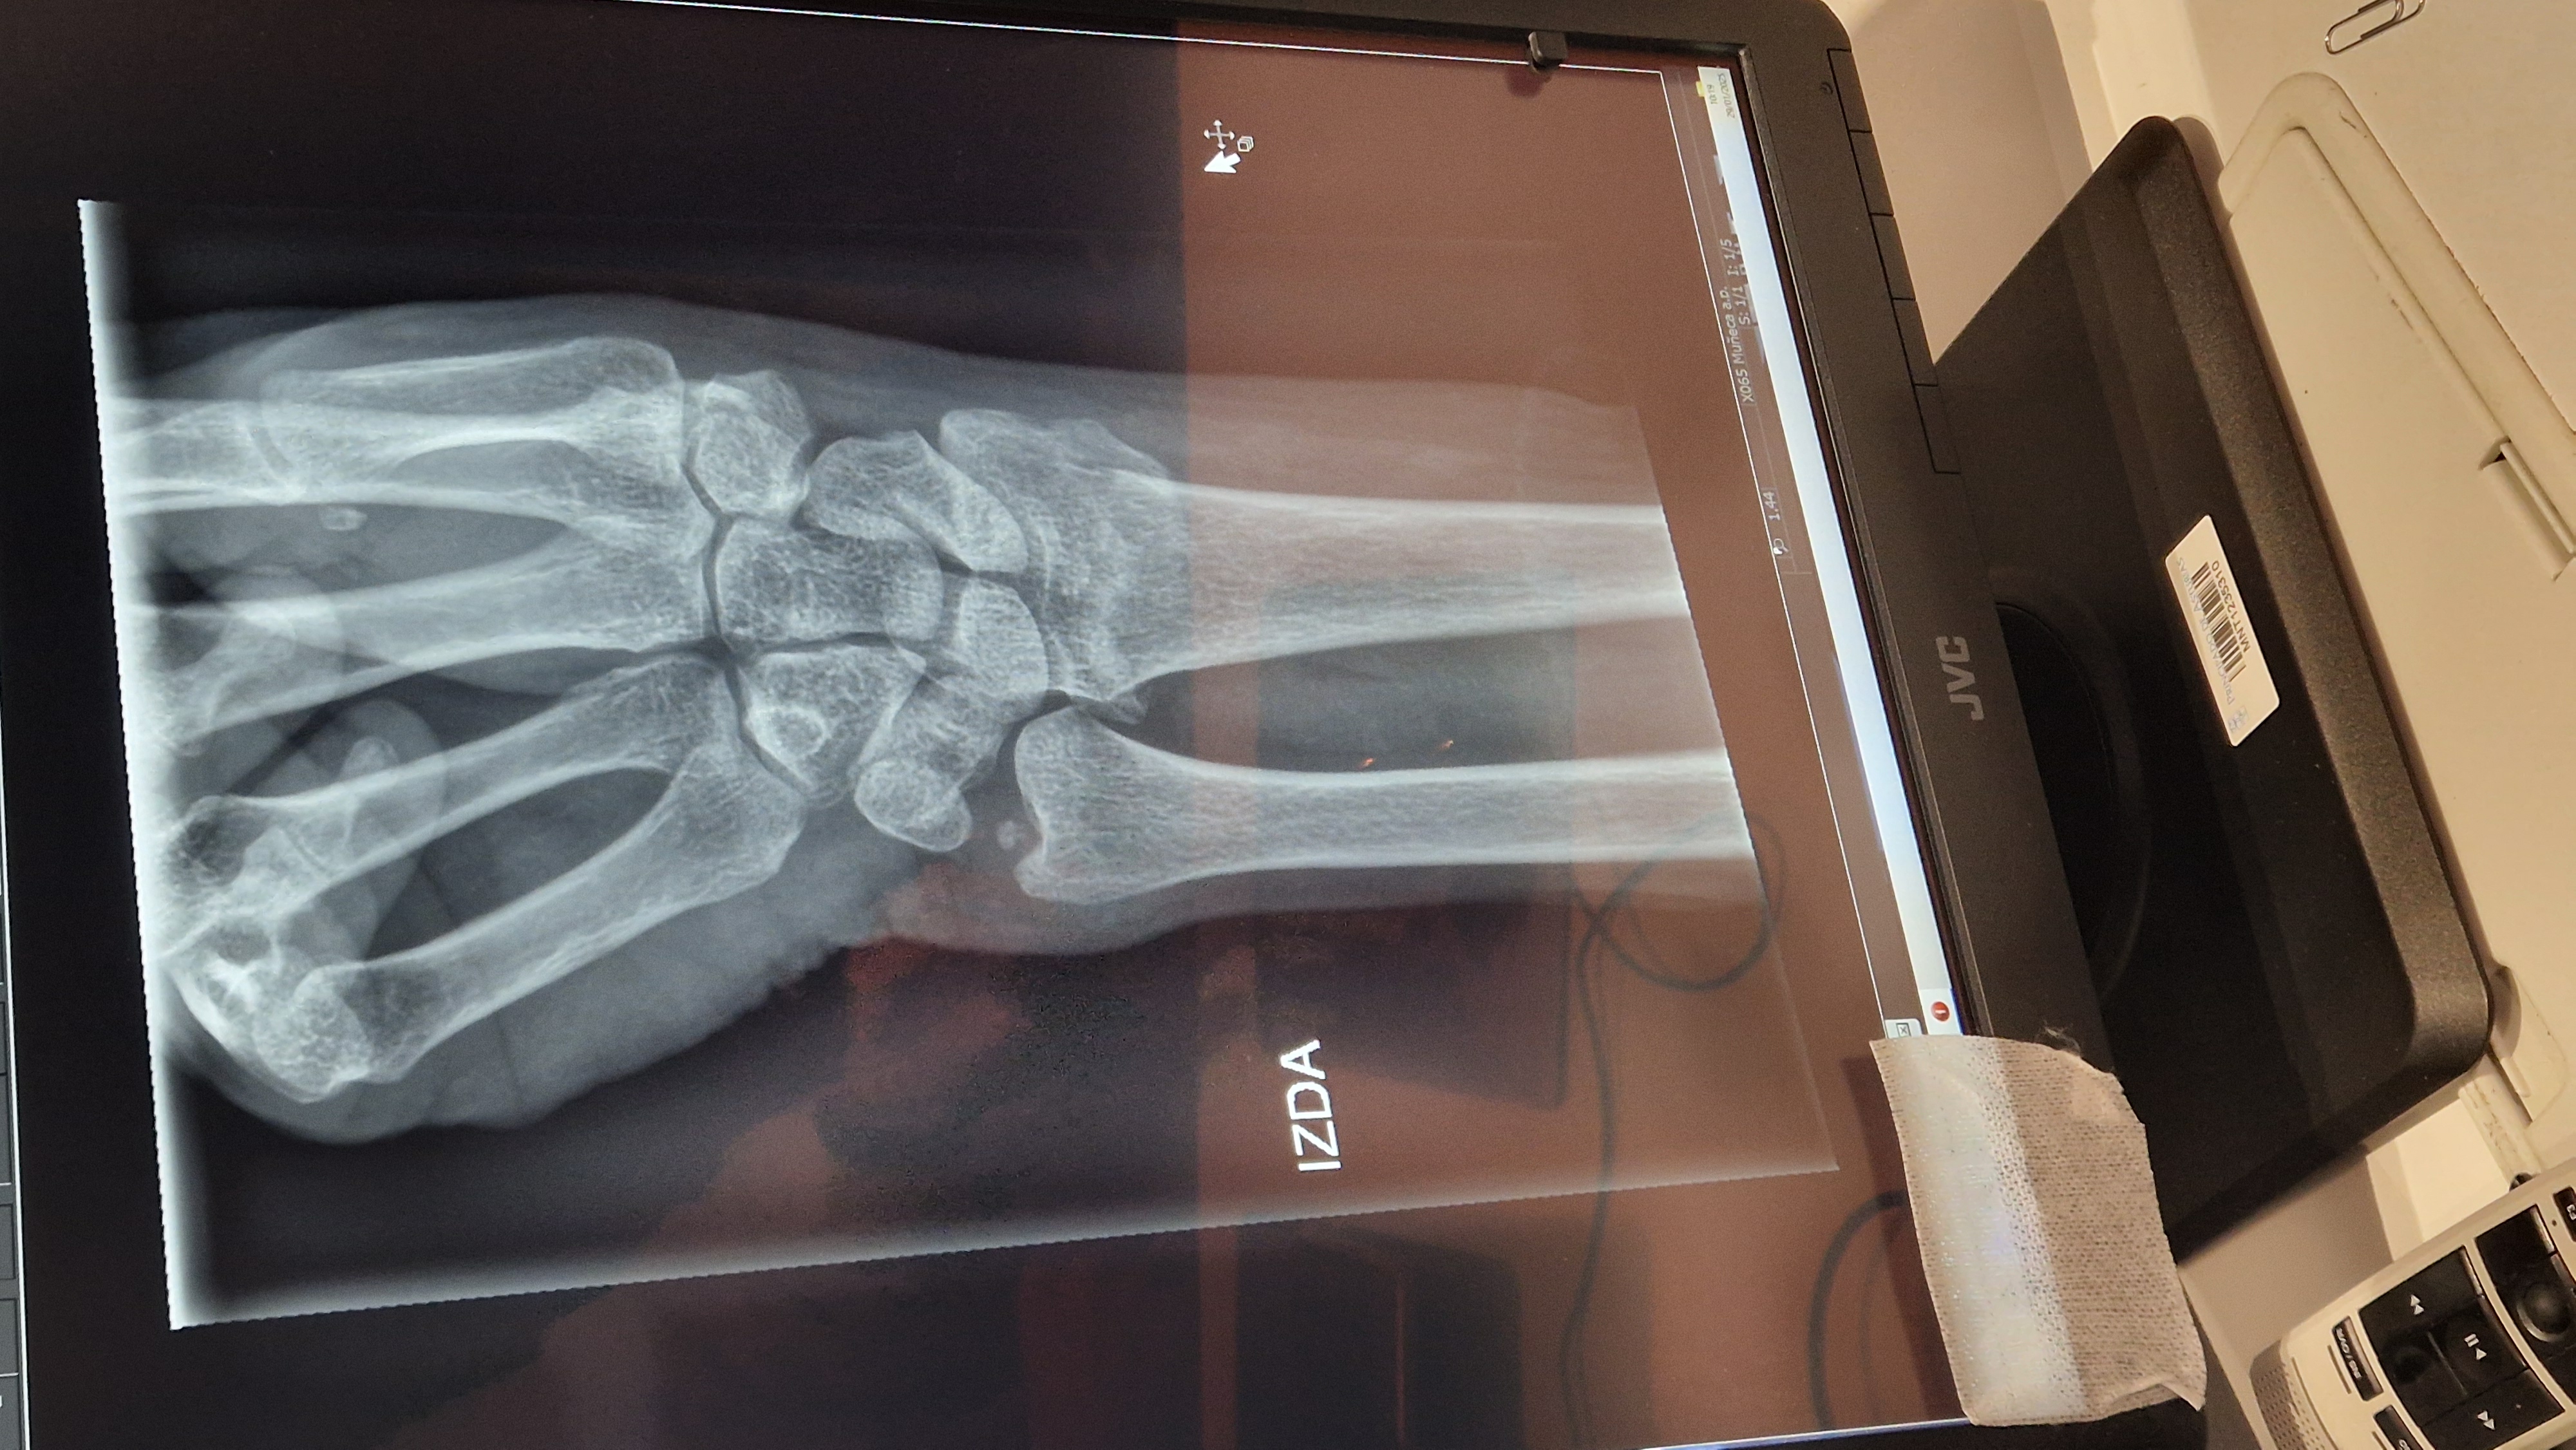

El primero de ellos, conocido como BoneView, ayuda a la toma de decisiones en el diagnóstico de fracturas. Tras la realización de una radiografía, la imagen se envía al sistema de archivo y comunicación de imágenes –conocido como PACS, donde se anonimiza y se devuelve analizada por la inteligencia artificial. En escasos segundos, se genera una segunda imagen que proporciona una evaluación de la presencia de fracturas, luxaciones o lesiones óseas y las localiza, mostrándolas directamente en la pantalla.

El examen se divide en tres categorías: presencia de fractura, sospecha de fractura o ausencia de fractura. Esa segunda imagen se almacena nuevamente en el PACS, junto con la radiografía inicial, y aporta toda la información para el diagnóstico.